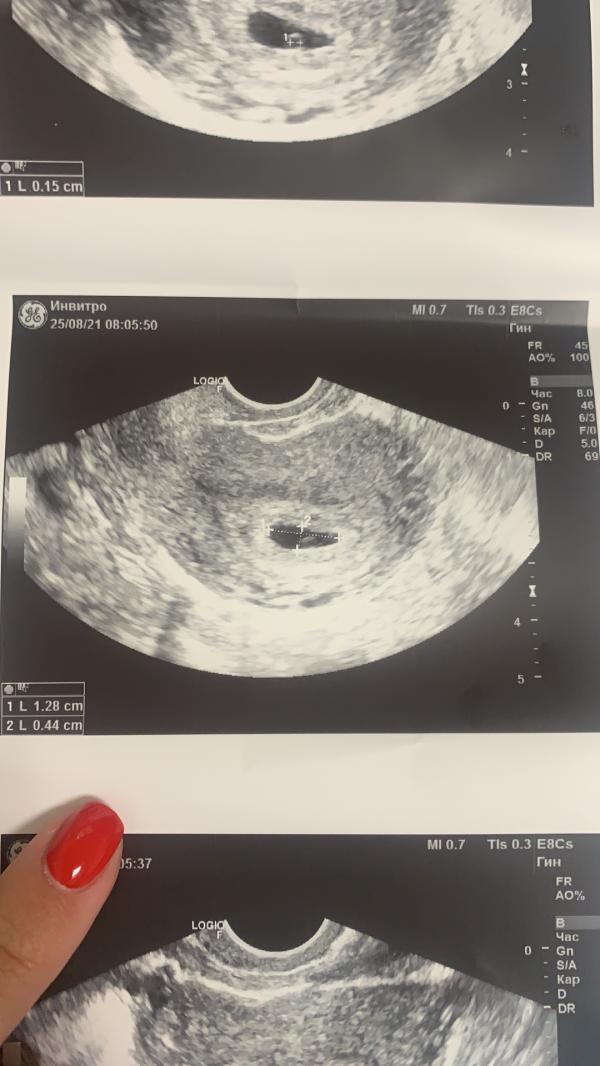

@larisa7778 это само плодное яйцо измеряли , ракурс отдалили и поэтому не видно. Не переживайте) через неделю все видно будет точно)

@larisa7778 для этих снимков нормальное заключение и рекомендация повторить УЗИ для отслеживания динамики))

Все видно! УЗИ аппарат не очень. И уже ж м есть! Просто эмбриончик маленький и на таком аппарате видимо решили его не измерять...